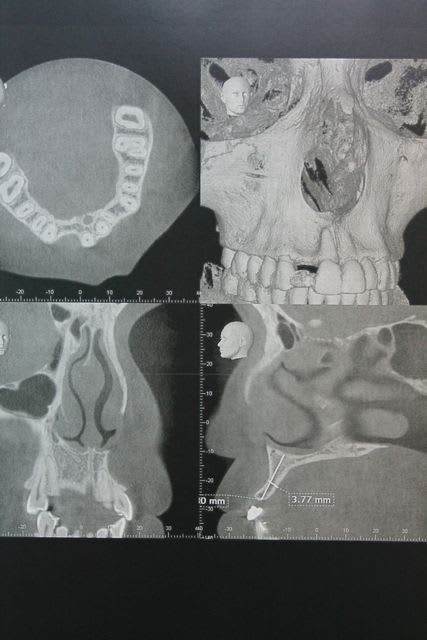

la suite et le début:

scan pré op: pas bcp d'os dispo au niveau de 46 47, y'a fallu aller plus loin derrière

la 11: voir son axe et le peu d'os autour en vestibulaire

photo de la cica à quelque mois

bientôt scan et pose de l'implant